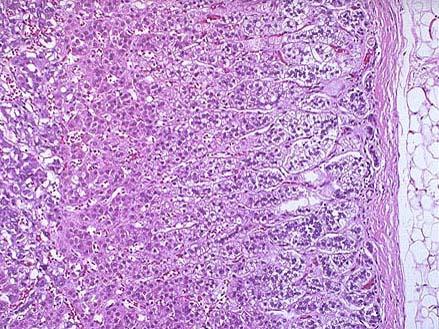

问题 正常肾上腺镜下如图所示,不正确的叙述为 ( )

选项 A.皮质可分三带,由外向内为球状带、束状带、网状带 B.球、束、网三带厚度比约为3:2:1 C.球状带细胞较小,由三五个细胞构成腺泡小球 D.束状带细胞较大,沿血窦作束状排列 E.束状带的细胞束彼此连接成网状构成网状带

答案 B